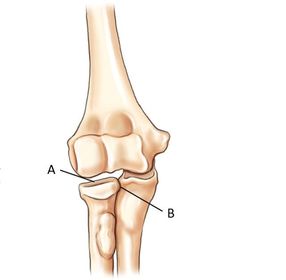

A. humerus B. coronoid fossa C. medial epicondyle D. humeral condyle E. trochlea F. trochlear sulcus G. radial head H. capitulum I. lateral epicondyle J. radial fossa

A. medial epicondyle B. trochlea C. coronoid tubercle D. radial head E. capitulum F. lateral epicondyle H. olecranon process